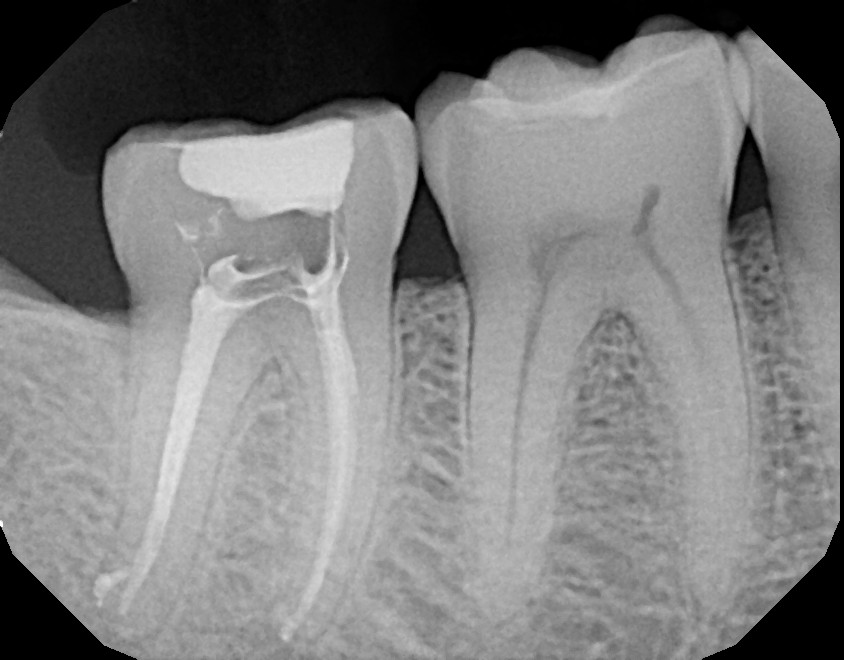

This second mandibular molar (tooth #31) never had any fillings in the past but started feeling sensitive to hot, cold, and bite. Upon examination, the tooth revealed a crack on the crown portion which required a root canal and crown. If this patient did not notify their dentist to refer them for an examination with an endodontist, tooth extraction would eventually become the only alternative. With proper treatment, this patient kept their tooth, saved a lot of money avoiding an implant, and had a dental night guard fabricated because they were a grinder/clencher who was damaging their teeth unknowingly.